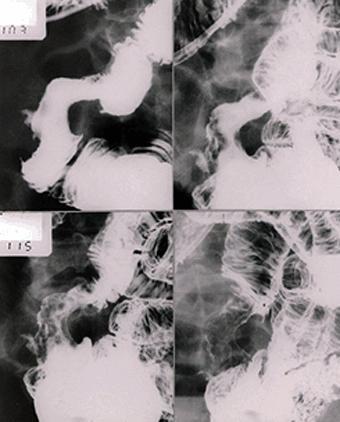

Criteria of Hist.ClassificationMalignant epithelial tumor/Adenocarcinoma

LocationSmall intestine/Ileum

Technique, MethodX-ray

Macroscopic TypesType 2 Ulcerated type with clear margin/

Size40 -

Depth of Tumor Invasionserosa (adventitia)